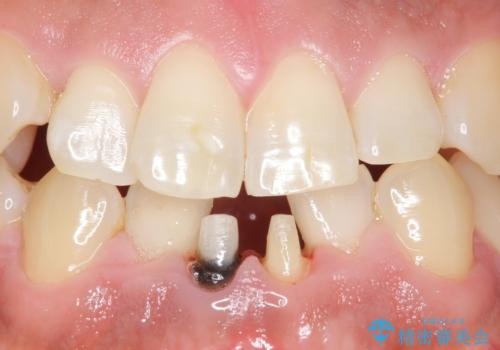

下の前歯の色が気になる セラミックで綺麗に 40代男性

- 下の前歯の色が気になることを主訴に来院された患者様です。

下の前歯は金属の土台により黒くなり、隣の歯も神経が死んで暗く変色していました。

神経が死んでいる歯の根管治療を行った後、セラミッククラウンによる補綴治療を行いました。

※右下1の再根管治療もおすすめしましたがご希望されませんでした。

※下顎前歯部の叢生について矯正も提案致しましたが、ご希望されませんでした。